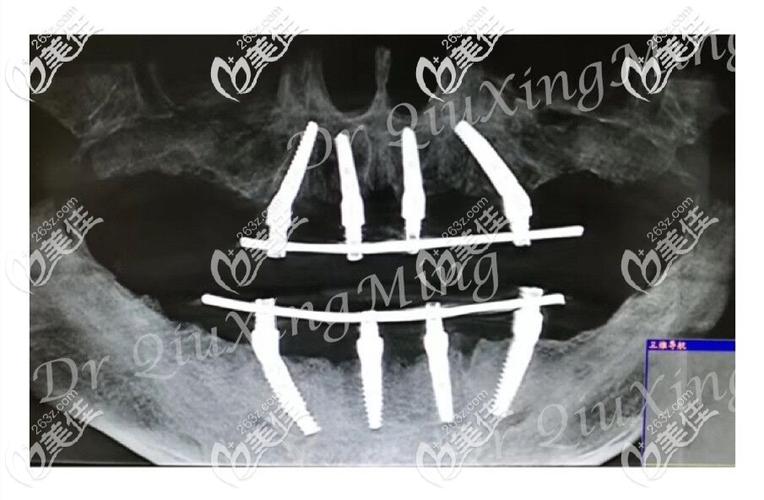

传统全口种植牙常需根据患者牙槽骨条件植入多枚种植体,而allon4通过“斜向种植+交叉支撑”的力学设计解决了骨量不足的问题,具体而言,在上下颌骨中,通常在前牙区植入2枚垂直种植体,后牙区植入2枚倾斜45°的种植体(倾斜角度可规避上颌窦、下齿槽神经管等重要解剖结构),4枚种植体形成稳定的三角形支撑结构,分散咬合力,确保牙桥长期稳定,这种设计不仅减少了对骨量的需求,还允许在种植体植入后立即安装临时牙桥,实现“当天种牙、当天用牙”的即刻负重效果,显著缩短治疗周期。

禁忌人群则包括:严重未控制的糖尿病、骨质疏松(需评估骨密度)、颌骨内有恶性肿瘤或放射性治疗史、严重夜磨牙或咬合异常、口腔内有急性炎症(如牙周炎、根尖周炎未控制者)等,术前检查需结合口腔CBCT、全景片、口内扫描及全身健康状况评估,重点测量牙槽骨高度、宽度,判断上颌窦底位置与下颌神经管走向,确保种植体植入路径安全。